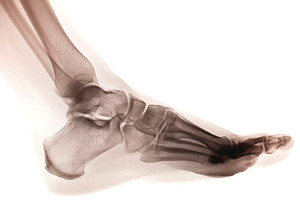

There are several bones in each foot, and a stress fracture occurs when there is a hairline break in one of the small bones. It often happens as a result of repetitive stress the feet endure from running or from frequently participating in jumping activities. The fractures are typically very small, despite how painful they can be. Many people choose to ignore the nagging pain in their foot, and it often becomes worse if it is not promptly treated. It may be a common injury among runners who increase their speed and frequency of running too soon, and this could gradually cause a stress fracture. This can be a result of a lack of strength and endurance from the muscles that cannot cope with added support that is needed when that activity increases. Additional reasons why stress fractures may occur include having an abnormal foot structure, wearing shoes that do not fit correctly, or having previous stress fractures. If you think you have endured this type of fracture, please speak with a podiatrist as quickly as possible who can properly treat this condition.

Stress fractures occur in the foot and ankle when muscles in these areas weaken from too much or too little use.  The feet and ankles then lose support when walking or running from the impact of the ground. Since there is no protection, the bones receive the full impact of each step. Stress on the feet can cause cracks to form in the bones, thus creating stress fractures.

To figure out the cause of foot pain, podiatrists utilize several different methods. This can range from simple visual inspections and sensation tests to X-rays and MRI scans. Prior medical history, family medical history, and any recent physical traumatic events will all be taken into consideration for a proper diagnosis.